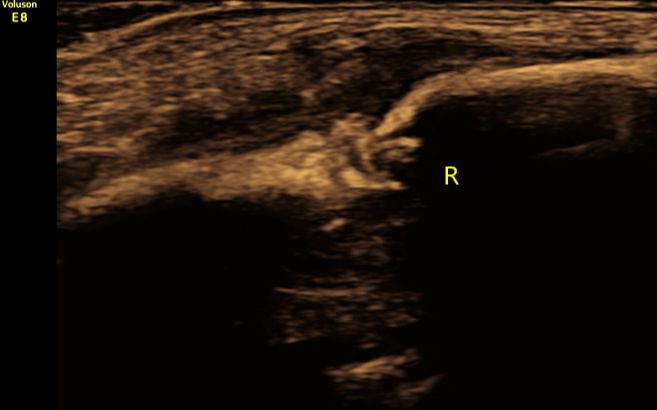

(图2:超声多切面显示右侧锁骨骨折断端)

①直接征象:超声二维显示锁骨骨皮质连续性中断,新鲜错位骨折时断端显示清晰,愈合期骨折处显示增厚、模糊;